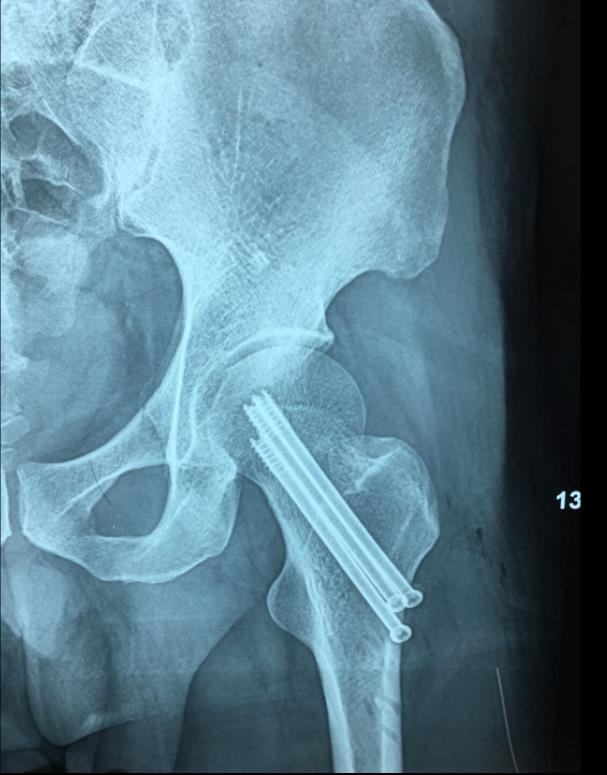

闭合复位经皮固定手术步骤

1、经皮沿股骨颈轴线置入空心钉导针,确保导针平行;

2、标准放置螺钉为倒三角形,其中下方螺钉在股骨矩,后方螺钉在后方骨皮质、研究发现倒三角形平行三枚螺钉能提供最佳的固定强度;

3、螺钉位于股骨颈四周,特别是后侧及下方,避免低于小转子方向进针,可能导致术后转子下骨折;

4、两个平面透视导针位置良好后切开皮肤,空心钻铭孔,导针引导下拧入空心钉,空心钉确保所有螺纹位于骨折线近端,螺钉头应距离软骨下骨5mm。

阳性支撑与阴性支撑

1、阳性支撑是指股骨颈骨折的远骨折端突向近侧骨折断端内下缘的内侧。

图3 阳性支撑更稳定

2、阴性支撑是指近侧骨折断端(股骨颈、头)的内下缘突向股骨颈远骨折端内上缘的内侧。阴性支撑容易导致复位的股骨头移位,继而发生内翻,内固定失败率高。

图4 阴性支撑不稳定